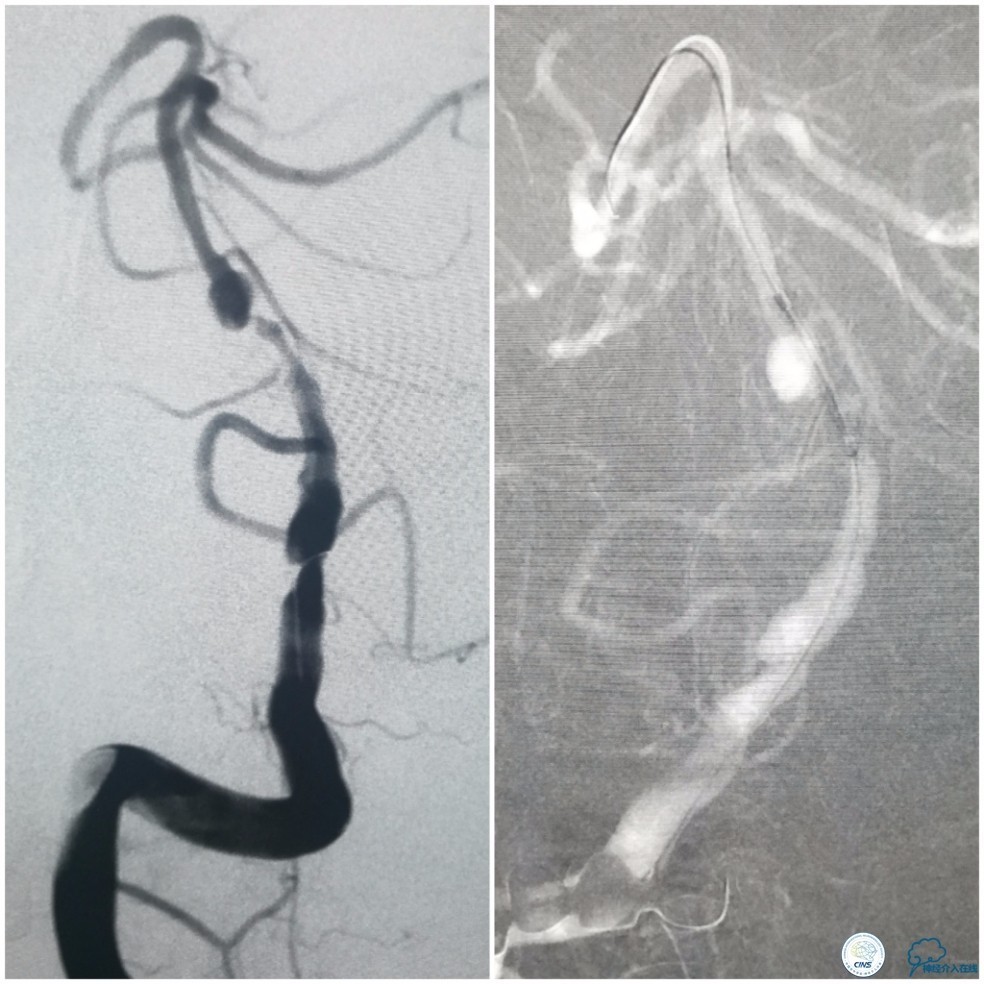

沿Echelon-10微导管依次推入EV3 PC-3-6-3D 3mm×6cm、QC-3-6-3D 3mm×6cm、QC-2-6-3D 2mm×6cm、QC 1.5-2-HELIX 1.5mm×2cm四个弹簧圈进入动脉瘤腔内。造影显示动脉瘤腔填塞致密(图12)。

图12

撤出Echelon-10微导管及5F导引导管。沿6F导引导管送入Select Plus微导管至基底动脉远端。经微导管送入Enterprise 4.5mm×28mm至右椎动脉V4段,两个支架重叠约2-3mm,完全覆盖右椎动脉V4段夹层(图13)。

图13